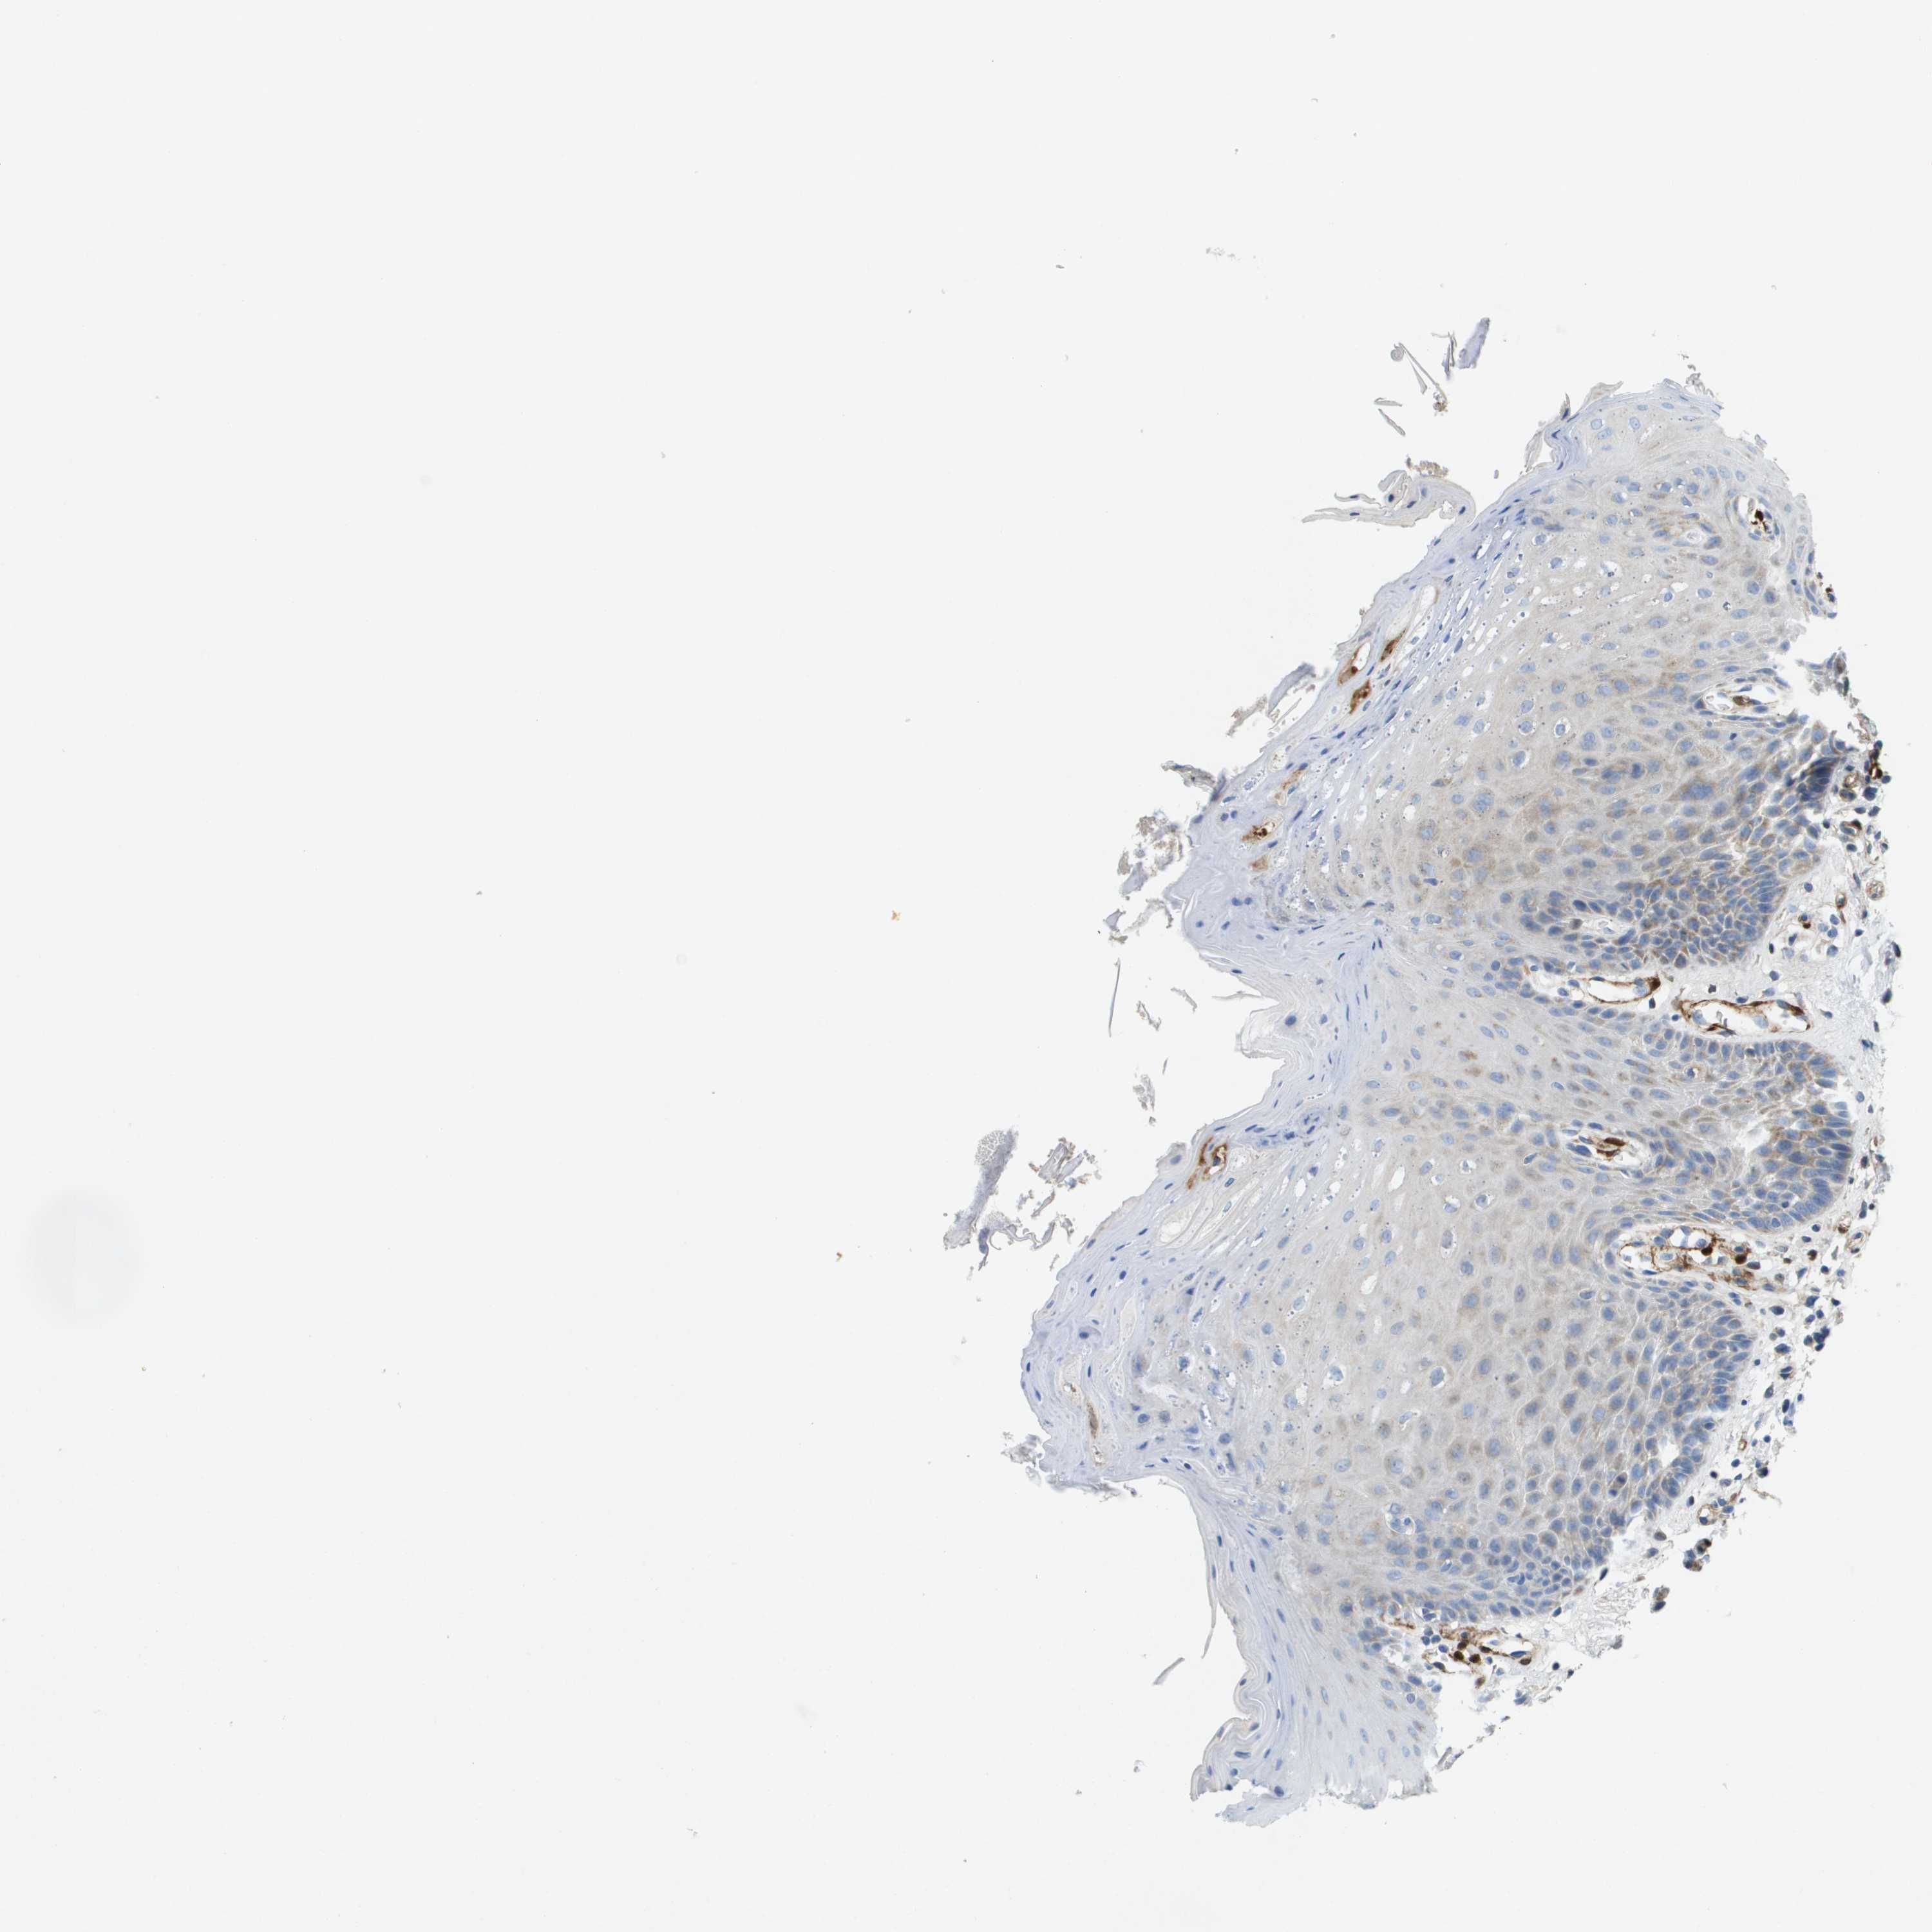

TISSUE PRIMARY DATA ORAL MUCOSA Show tissue menu

ORAL MUCOSA - Antibody stainingi

Antibody staining in the annotated cell types in the current human tissue is reported as not detected, low, medium, or high, based on conventional immunohistochemistry profiling in selected tissues. This score is based on the combination of the staining intensity and fraction of stained cells.

Each image is clickable and will lead to virtual microscopy that enables deeper exploration of all samples and also displays staining intensity scores, fraction scores and subcellular localization as well as patient and tissue information for each sample.

Antibody HPA017757

Squamous epithelial cells Not detected